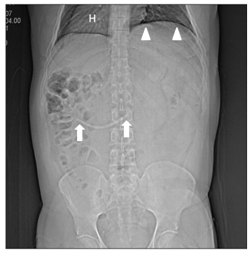

During the six years following laparoscopic cholecystectomy, the patient undergoes frequent medical examinations due to multiple episodes of acute cholangitis that require endoscopic dilatation of the stenosis and placement of biliary stents through endoscopic retrograde cholangiopancreatographies (ERCP) until, finally, the patient had a biliodigestive (Roux-en-Y) anastomosis. During surgery, the stent is not removed as it is not visualized and, based on the suspicion of a possible distal migration, a radiograph of the abdomen is requested, in which the prosthesis seems to be found in the hepatic angle of the colon (Figure 6). Over five months the patient was asymptomatic, and the stent, presumably in transit, was controlled through radiographs but it does not seem to change its location. In view of the above, it is decided to perform a computerized tomography to accurately locate the prosthesis (Figures 7-8), it was shown that it was located in the duodenum with the distal end in the region of the jejunal anatomy, since it had not managed to circumvent the angulation that occurs in the efferent jejunal loop just after the anastomosis.

Figure 6 Abdominal radiography shows the displaced stent (arrows).

Stent migration is considered a rare event, occurring in 5-10% of malignant processes, and with higher incidence in benign processes due to inflammation,9,12,13 as in our patient. In addition, migration has been reported to be more frequent with plastic prostheses,11 used in benign stenosis, as in this patient (Figure 7). Distally migrated stents normally pass through the gastrointestinal tract (86% of cases).10,14,15,16 For this reason, initial management for the patient was expectant, with thorough and prolonged follow-up by abdominal x-rays17 ( Figure 6). A lower percentage of prostheses remain in the intestine without symptoms10,14,15,16 as in the presented case. Thus, after a 5-month follow-up with abdominal x-rays, where no significant changes were observed in the location of the prosthesis, it was decided to perform an abdominal CT scan, both to locate the stent and to provide the endoscopist with detailed information of the abnormal post-surgical anatomy of the patient's upper gastrointestinal tract.23 Lastly, the prosthesis was localized in the duodenum with its distal end in the area of jejunojejunal anastomosis (Figure 8). We understand that at the beginning of the surgical Roux-en-Y hepaticojejunostomy there was a migration of the prosthesis, which remained in the duodenum until the end of the procedure. Subsequently, due to the angle in the segment of the anastomosis, the prosthesis failed to progress through this area remaining in the same location during the five months of follow-up (Figure 9).